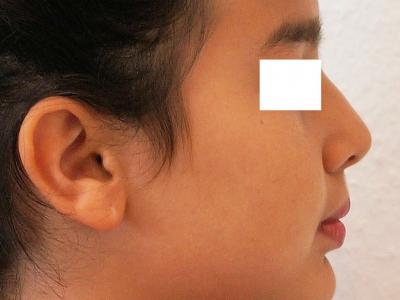

Figure 4 : patiente de 9 ans présentant un déséquilibre mécanique de la région incisivo-canine mandibulaire se traduisant par un sillon labio-mentonnier marqué (a) avec empreinte cutanée (b), une rétroalvéolie mandibulaire globale (c) et un parodonte affaibli avec profondeur vestibulaire réduite (d).

Figure 8 : prise en charge d’une rétroalvéolie et rétrochéilie mandibulaire à 13 ans par affaiblissement labio-mentonnier et traitement orthodontique

Profil avant traitement (a),

profil après 2 ans de traitement et 1 an de contention, montrant l’avancée labiale et la diminution de la progénie (b)